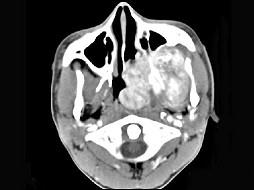

问题 男性,19岁,左侧鼻腔反复出血一年余,CT、MRI扫描如图所示,请选择最可能诊断 ( )

选项 A、鼻咽癌 B、鼻咽部淋巴瘤 C、鼻咽腔脓肿 D、鼻咽部青年纤维血管瘤 E、鼻息肉

答案 D